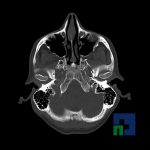

- Diagnosticul traumatismelor de bază de craniu

- Diagnosticul fracturilor:

- Complexe cranio-sinusale

- Complexe cranio-etmoidale

- Complexe cranio-orbitare